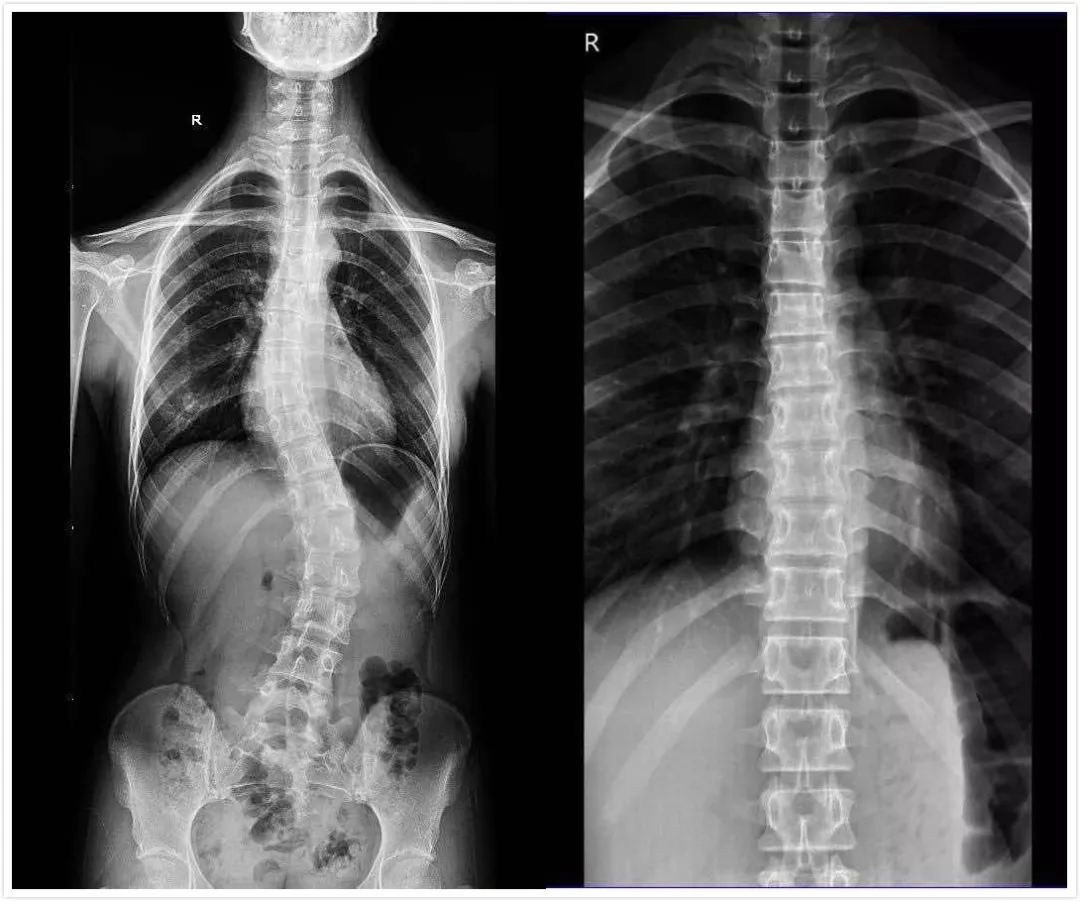

驼背廿年,巧治变高